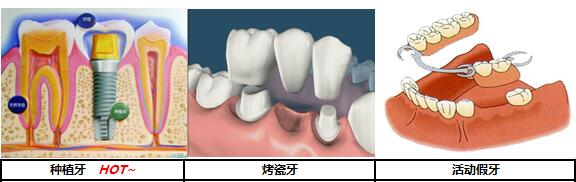

说到牙齿缺失修复,很多人先想起的就是镶牙,传统的假牙一般是用金属杆或卡环固定在两侧的健康牙上,或者是利用塑料基托直接骑跨在缺牙牙床上,靠口腔唾液吸附。不仅不够牢固,还影响面部美观,异物感强烈,咀嚼力也是不够的。这远远不能够满足现代年轻人的需求。

后来出现了如今比较热门的烤瓷牙,但烤瓷牙也有很大的弊端,做普通的烤瓷牙冠,首先需要把两边的牙齿磨掉,形成两个“桥墩”,然后在上面做个冠桥,这样两颗牙就支撑起了三个牙冠。这样的修复方式较大的问题是咬合力不足。因为只有两个牙根,却要实现三颗牙的功能,自然是不现实的。>>>缺失一颗牙修复多少钱?在线咨询<<<

种植牙的出现,成功解救了那些为缺牙而苦恼的年轻男女们。

种植牙和真牙一样,分为牙根和牙冠两大部分。种植牙牙根由高强度、高安全性的钛金属制成,将种植牙牙根植入缺牙部位的颌骨中,经过一段时间,种植牙牙根就会与周围的骨质牢牢“长”在一起,形成良好、稳定的骨结合,起到类似真牙牙根的作用。这样,再大的咀嚼力量也能够承受,做到稳固不晃。无论是坚硬食物,还是黏性食物,患者即可尽情地吃,和真牙完全一样。>>>种植牙价格是多少?在线咨询